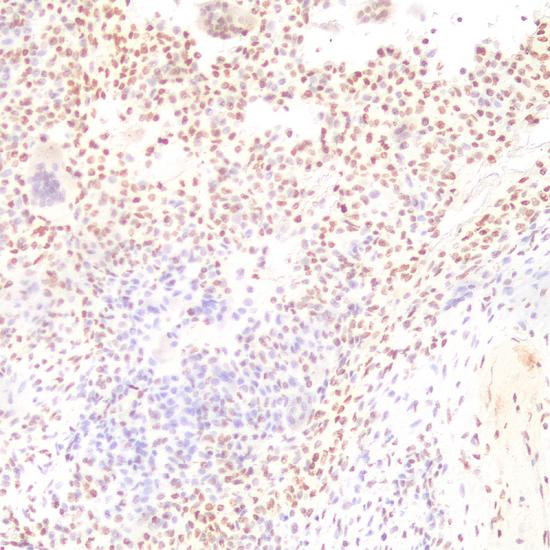

H3K36M

兔抗人組蛋白H3第36位上的賴氨酸甲基化單克隆抗體

細(xì)胞核

軟骨母細(xì)胞瘤

H3K36M突變通過抑制特定的組蛋白甲基轉(zhuǎn)移酶(HMTs),改變腫瘤基因組整體水平的表觀修飾水平,參與腫瘤的形成和進(jìn)展。研究表明超過95%的軟骨母細(xì)胞瘤存在組蛋白H3K36M突變,H3K36M突變是一種腫瘤發(fā)生的驅(qū)動突變。